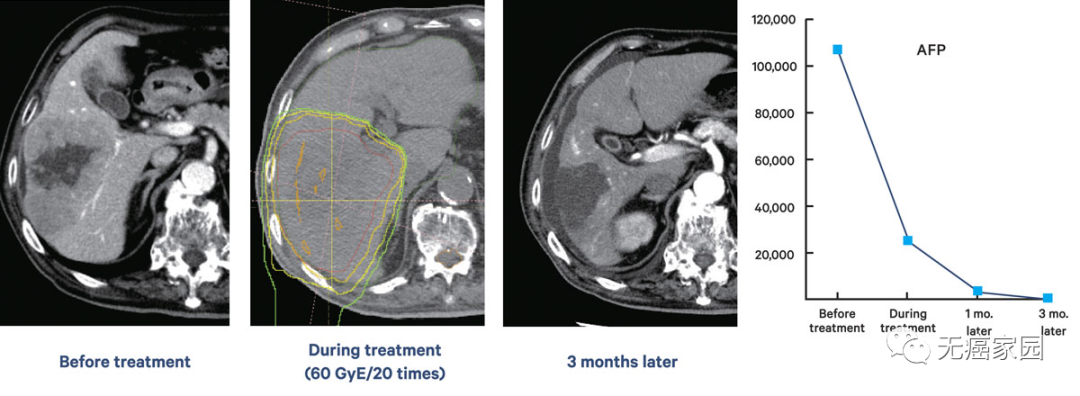

临床研究表明,质子治疗可带来许多出色的结果,通常可以治愈以前公认无法治愈的癌症。例如,一名80年代无法手术的肝细胞癌患者接受了20次质子束治疗后,在治疗开始后的3个月内,肿瘤大小显著缩小,肿瘤标志物水平显著下降。在最近的一项研究中发现,鼻咽癌患者在质子治疗后并未失去其味觉。他说:“我很吃惊,因为接受标准放射治疗的鼻咽癌患者会失去味觉。” 副作用的减少是质子治疗的巨大优势。

以上为一例80多岁男性的肝细胞癌示意图。图像显示治疗前,质子束照射20次后和3个月后的肿瘤标志物的水平。随着治疗的进展,甲胎蛋白(AFP)和异常凝血酶原(DCP,又称为PIVKA-II)逐渐下降。